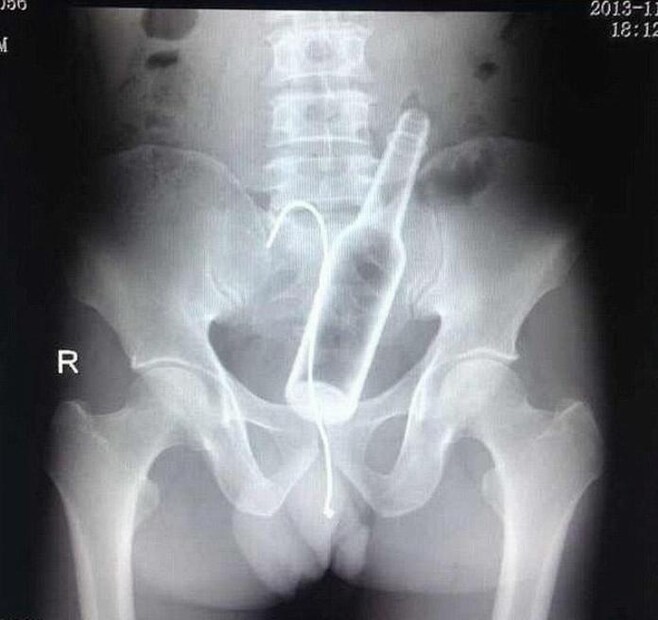

পৃথিবীতে অনেক ধরনের পাগল আছে। কিছু মানুষ মজার নামে এমন হাস্যকর কাজ করে বসেন, যার পরিণতি হয় ভয়াবহ। এমন অনেক ঘটনা সামনে আসে, যেখানে ব্যক্তি গোপনাঙ্গে অদ্ভুত কাণ্ড করে বসেন। এমনই একটি ঘটনা সামনে এসেছে চিন থেকে। এখানে বসবাসকারী এক ব্যক্তি মজা করে নিজের গোপনাঙ্গে ব্যাটারি রেখে ফেলেছিলেন। এরপর লজ্জায় চিকিৎসকের কাছে যাননি। কিন্তু একদিন পর যখন ব্যথা সহ্যের বাইরে চলে গেল, তখন চিকিৎসকের পরামর্শ নেন তিনি। এরপর তার এক্স-রে রিপোর্ট দেখে সবাই অবাক হয়ে যান।

৪৯ বছর বয়সি এই ব্যক্তির জরুরি অস্ত্রোপচার করা হয়েছিল। এই এএ ব্যাটারিটি তার গোপনাঙ্গে আটকে গিয়েছিল। এই ব্যাটারি কী ভাবে ভিতরে ঢুকল জানতে চাওয়া হলে তিনি বলেন যে তিনি মজা করার জন্য এটি করেছিলেন। কিন্তু তখনই হাত থেকে ব্যাটারি পড়ে ভিতরে চলে যায়। ব্যাটারি বের হতে পারেনি। সারাদিন তার শরীরে ব্যাটারি রয়ে যায়। এ কারণে তার প্রস্রাবে খুব কষ্ট হচ্ছিল। একদিন পর ব্যাটারিটি বের করে দেওয়া হয়। কিন্তু পাঁচ মাস পর আবারও সমস্যা শুরু হয় ওই ব্যক্তির।

মেডিক্যাল টিম জানান, অনেক সময় এমন হয় যে বাইরের জিনিস শরীরের ভেতরে চলে গেলে অনেক ঝামেলা হয়। বিশেষ করে ব্যাটারি ভিতরে বিষাক্ত রাসায়নিক পদার্থ পূরণ করে। এ কারণে ওই ব্যক্তির প্রস্রাবে সমস্যা দেখা দেয়। এ ধরনের বোকামি না করার পরামর্শ দিয়েছেন চিকিৎসকরা। এই ধরনের ফরেন এলিমেন্ট শরীরের দীর্ঘমেয়াদি ক্ষতি করে বলেও জানান চিকিৎসকেরা।